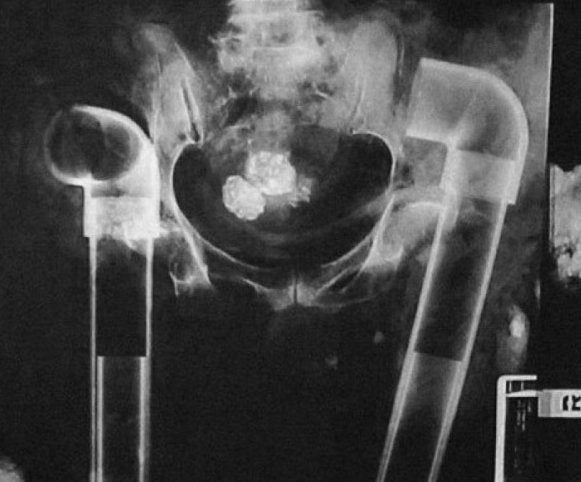

prisoners

X-rays from Central Prison in Raleigh, N.C., on display in May 2006 show items such as bed springs and batteries that prisoners swallowed to gain trips to outside hospitals.